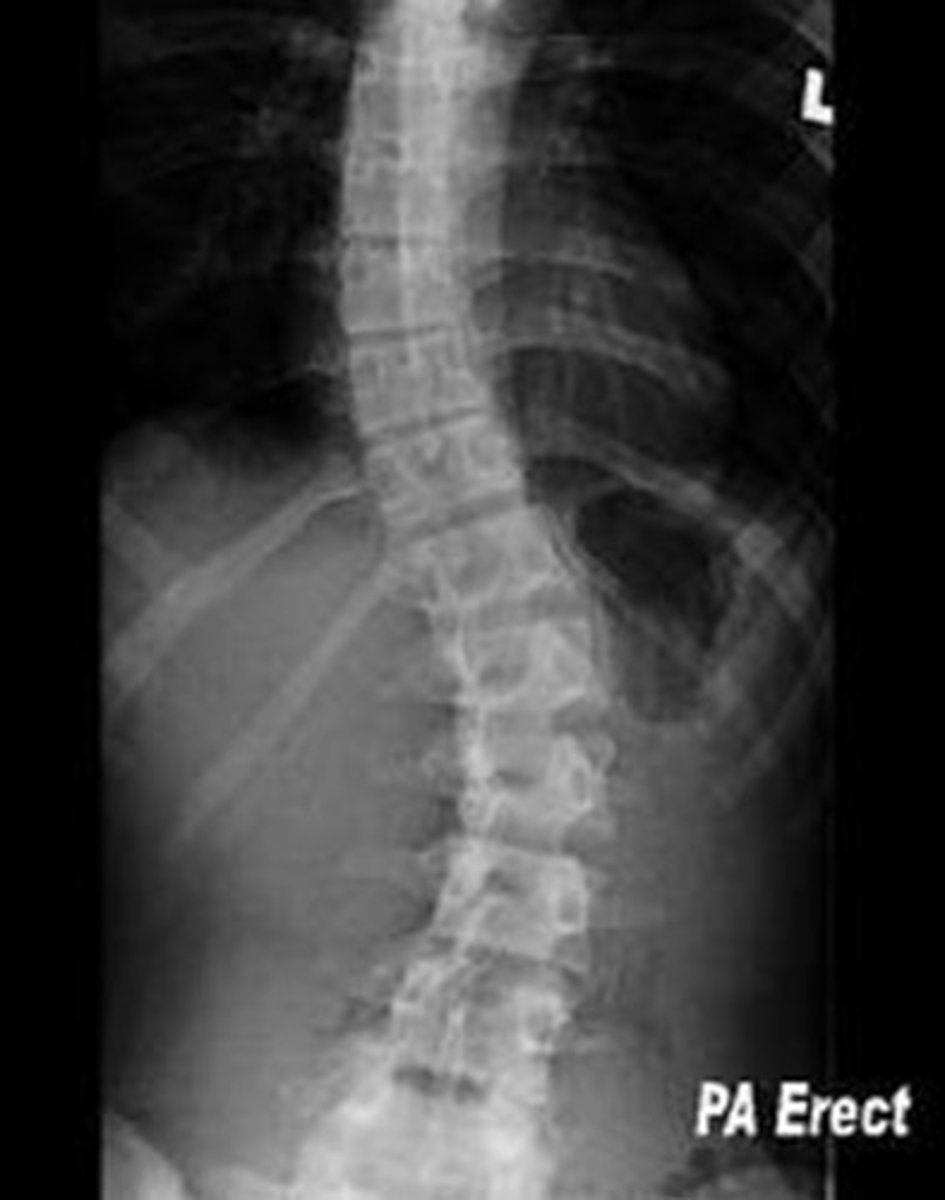

scoliosis

abnormal lateral curvature of the spine in the frontal plane with vertebral rotation

convexity

Scoliosis is named based on the side of _________________.

ex. R scoliosis in image